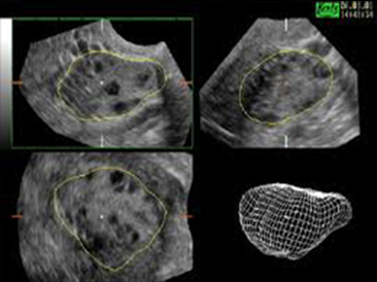

Όταν αναγνωρισθεί η περιοχή ενδιαφέροντος, τίθεται πλαίσιο οριοθέτησης και με σταθερή την υπερηχογραφική κεφαλή αρχίζει η εξέταση. Γίνεται αυτόματη σάρωση 360ο της περιοχής ενδιαφέροντος. Το τελικός αποτέλεσμα είναι η παρουσία 3 πλάνων, τα οποία μπορούν να μετατοπισθούν ή να περιστραφούν γύρω από τους άξονες x, ψ, z. Ο ανασχηματισμός των 3 εικόνων και η τελική σύνθεση μιας μόνο εικόνας προσφέρει ακριβέστερη μορφολογική εκτίμηση του όγκου του σώματος της μήτρας χωρίς να απαιτείται ιδιαίτερος χρόνος, μειώνοντας παράλληλα την δυσφορία αναμονής της ασθενούς.

Τα 3 πλάνα που εμφανίζονται στην οθόνη είναι:

α) το άνω αριστερό πλάνο (στεφανιαίο), «α», β) το άνω δεξιό πλάνο (οβελιαίο), «β», γ) το κάτω αριστερό πλάνο (εγκάρσιο), «γ». Στο κάτω δεξιό πλάνο εμφανίζεται η εικόνα «δ» μετά από τροποποίηση και επεξεργασία των 3 εικόνων («α», «β», «γ»).Για πληρέστερη αξιολόγηση του υπό εξέταση οργάνου και την επίτευξη του όσο το δυνατόν καλυτέρου αποτελέσματος απεικονιστικής ευκρίνειας, γίνεται χρήση ειδικών μεθόδων (modes):